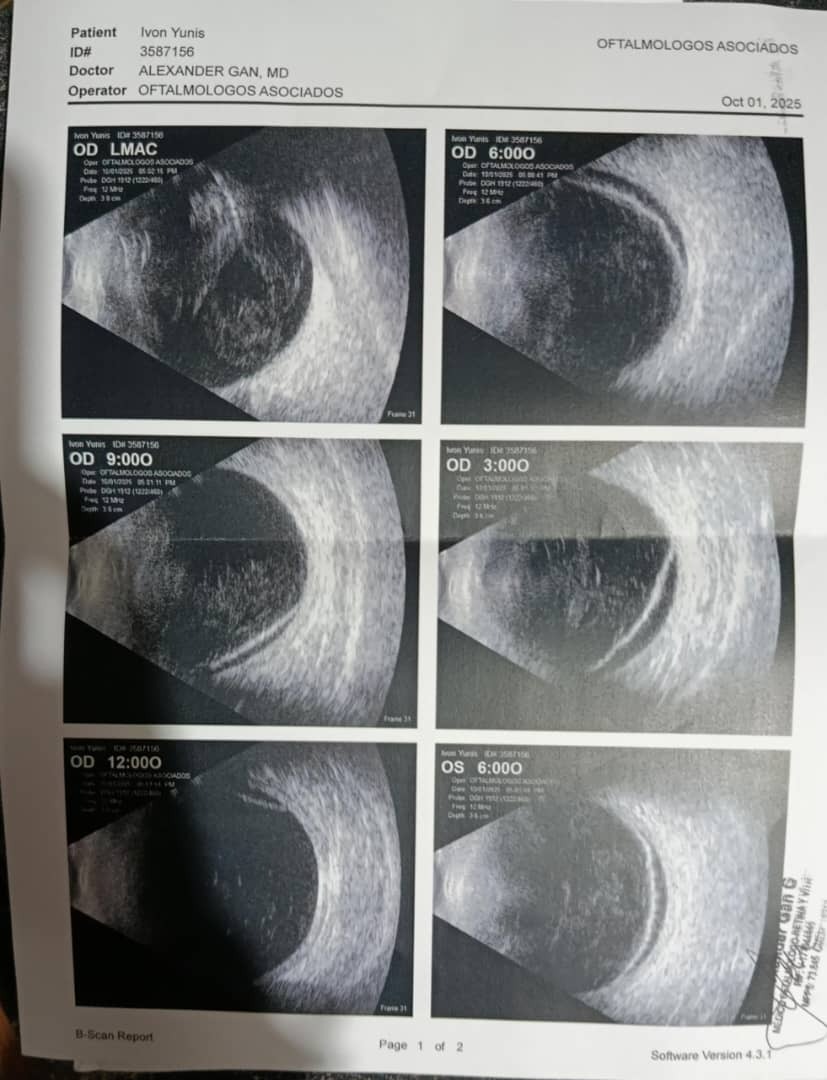

Hoy se está quedando ciega. Tiene un desprendimiento de retina en ambos ojos. La Tienen que operar cuanto antes, para que no pierda la visión. Por eso estoy aquí, pidiendo ayuda. Porque mi mamá se está quedando ciega en un país donde los sueños no están rotos, pero si que cojean. Y a pesar de tener de nuevo el apoyo de muchos vecinos que más que vecinos son familia, por más que ha visto a varios médicos y buscado las opciones más económicas, mi hermano y yo no podemos costear los gastos médicos. Créame, lo hemos intentado todo, pero algunas batallas cuestan más que otras, y está, sin ayuda, no sé cómo superarla.

Por eso estoy aquí, pidiendo tu apoyo monetario, para que mi mamá no se quede ciega. Necesitamos 13.300 euros para poder cubrir las operaciones. Son cuatro: dos por cada ojo. Y no, no hay manera de hacer solo una operación. Tienen que ser cuatro operaciones, dos por cada ojo.